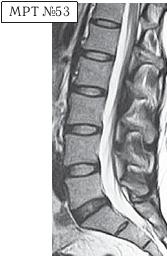

На МРТ № 53 — поясничный отдел позвоночника. На данном «контрольном» снимке, после устранения методом вертеброревитологии секвестрированной грыжи межпозвонкового диска в сегменте LV-SI, наблюдаются остаточные явления дегенеративного процесса. Но в целом состояние поясничного отдела позвоночника, отображённое на этом снимке, довольно хорошее, поэтому будем использовать его для сравнения как вариант нормы.

На МРТ № 54 наблюдается изменение физиологического лордоза, стеноз спинномозгового канала, грыжа межпозвонкового диска и спондилёз в сегменте LIII-LIV, ретроспондилолистез — LIV и LV. Как правило, причина вышеупомянутых болей при таких патологиях скрывается в дугоотростчатых суставах. Дело в том, что при изменении физиологического лордоза извращается «работа» и дугоотростчатых суставов. В состоянии нормы дугоотростчатые суставы имеют дугообразную форму и расположены во фронтальной, горизонтальной и сагиттальной плоскостях в среднем под углом 45о. При развитии дегенеративнодистрофического процесса в межпозвонковом диске (снижении высоты диска, возникновении сегментарной нестабильности) происходит смещение суставных поверхностей дугоотростчатых суставов по отношению друг к другу, что в свою очередь приводит к уплощению физиологического лордоза и его кифозированию (МРТ № 55) или же формированию гиперлордоза (МРТ № 56). И в том, и в другом случае данные процессы, как правило, сопровождаются сдавлением спинномозговых корешков (что вызывает соответствующие боли). Кроме того, сами дугоотростчатые суставы хорошо иннервированы, поэтому протекание патологических процессов, с участием этих суставов, сопровождается соответствующими болевыми ощущениями. ![]() На МРТ № 55 наблюдается уплощение физиологического лордоза в поясничном отделе позвоночника. На МРТ № 56 наблюдается гиперлордоз в поясничном отделе позвоночника. На МРТ № 57 наблюдаются нарушения конгруэнтности в дугоотростчатых суставах в сегменте LV—SI (указано стрелкой) вследствие гиперлордоза. ![]() |